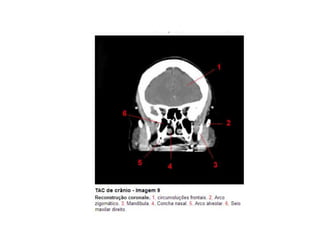

Anatomia E Protocolo Tomografia Computadorizada de Crânio PPT